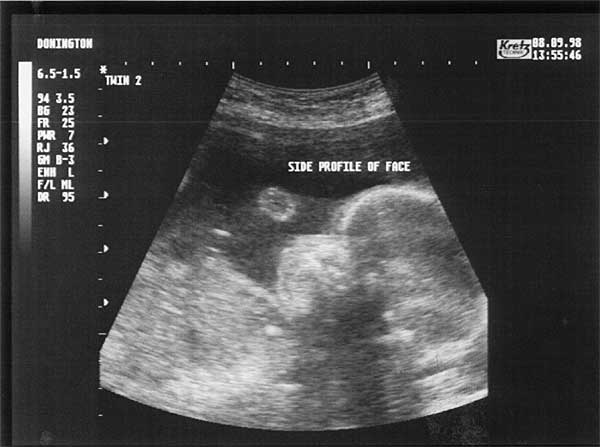

24 Weeks - Tuesday 8th September 1998.

Twenty Four Week Scan 3